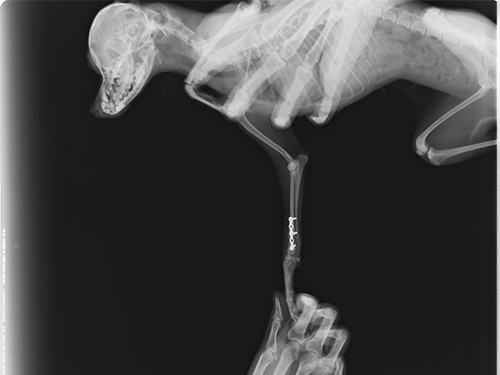

图4:侧位片(术后两周复查,可见骨折部位对接生长)